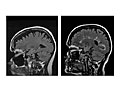

Magnetic resonance imaging (MRI) is a test that uses a magnetic field and pulses of radio wave energy to take pictures of the head. In many cases, MRI gives information that can't be seen on an X-ray, ultrasound, or computed tomography (CT) scan.

For an MRI of the head, you lie with your head inside a special machine (scanner) that has a strong magnet. The MRI can show tissue damage or disease, such as infection or inflammation, or a tumor, stroke, or seizure. Information from an MRI can be saved and stored on a computer for more study. Photographs or films of certain views can also be made.

A magnetic resonance imaging (MRI) test is done by an MRI technologist. The pictures are read by a radiologist. But some other types of doctors (such as a neurologist or neurosurgeon) can also read an MRI scan of the head.

During the test

During the test you will lie on your back on a table that is part of the MRI scanner. Your head, chest, and arms may be held with straps to help you lie still. The table will slide into the space with the magnet. A device called a coil may be placed over or wrapped around your head.